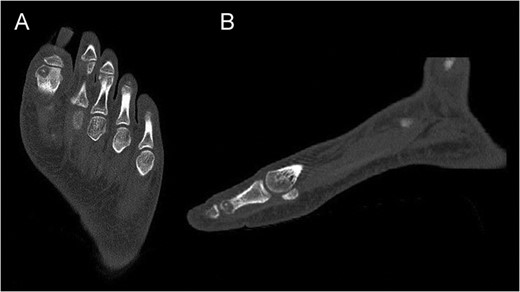

Preoperative CT of the proximal phalanx of the left hallux: axial (A), and sagittal view (B), showing the osteolytic nidus of the tumor with central calcification surrounded by a slight sclerotic halo: the standard image of OO.